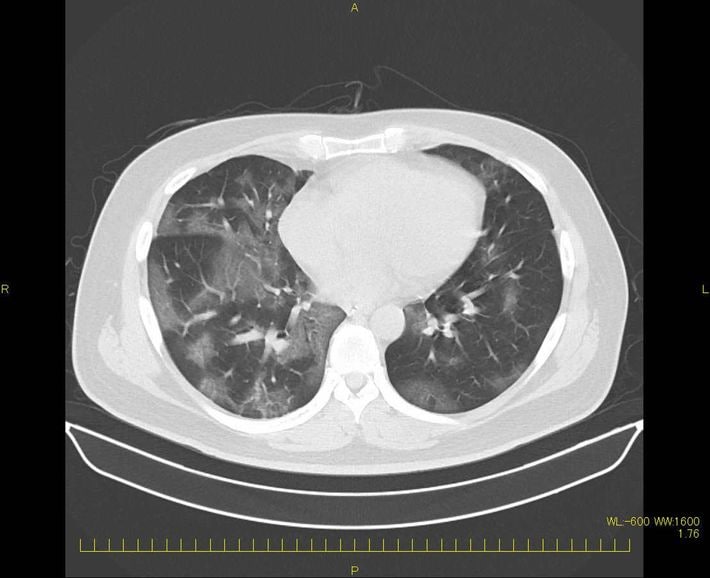

新型コロナに感染した外科医の肺CT画像